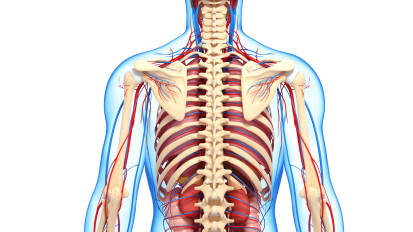

Innovation and Personalized Treatments in Spine Tumor Surgery: Pathology, Biomarkers and Genetics

Johns Hopkins neurosurgeon Daniel Lubelski discusses the importance of pathology, biomarkers and genetics in treatment of spine tumors. Immunotherapy and targeted therapies are used to approach tumors that have been bio-banked and gene-sequenced, resulting in a tailored treatment plan. This, combined with advanced medical and surgical options, is leading to the best possible outcomes for patients with spine tumors.